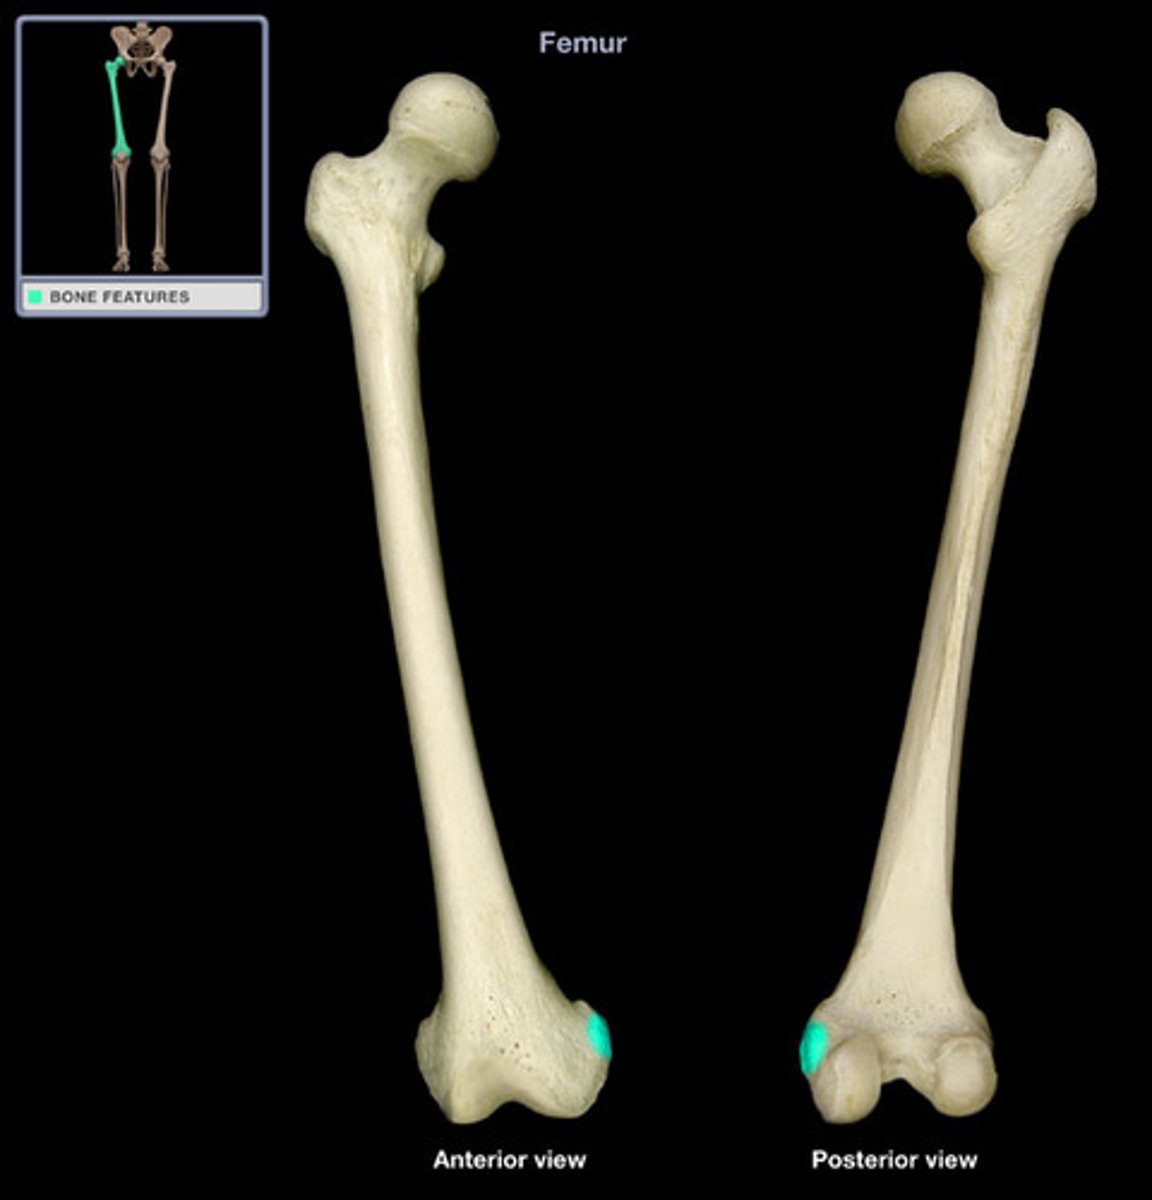

Femur

Medial Condyles of the Femur

Lateral Condyles of the Femur

Medial Epicondyles of the Femur

Lateral Epicondyles of the Femur